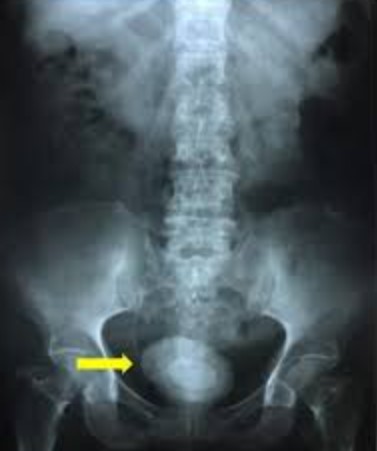

Diverticulum of bladder is a condition where the bladder lining protrudes through a weak or defective part of the bladder wall, forming a pouch or bulge that connects to the bladder lumen.

Bladder diverticula can be found with an x-ray test of the bladder. The test is done by filling the bladder with a dye that shows up well in x-rays (called a "contrast") and taking pictures. Your health care provider may also look into your bladder with a cystoscope, a long, thin telescope with a light at the end.